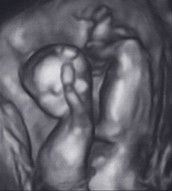

BEL 29SSW

Hallo.War heute bei meiner FÄ und meine kleine liegt immer noch mit dem Kopf nach oben.Sie hat schon erwähnt,dass ich mir das aussuchen kann,ob ich normal entbinden möchte od.halt per KS(Beckenendlage).Ich hoffe natürlich,dass sich meine kleine noch dreht.Aber haben die eigentl.noch soviel Platz zum drehen???weil Hoffnung hat sie mir nicht wirkl.gemacht!!!

Wie sind eure Erfahrungen mit BEL,bis zu welcher Woche können sie sich drehen???